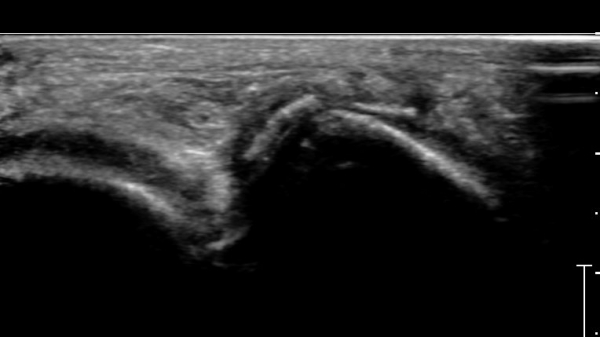

ÃÊÀ½ÆÄ°Ë»ç :  Àü°ÅºñÀδë Á¾´Ü¸é°Ë»ç¿¡¼­ Àü°ÅºñÀδëÀÇ Àú¿¡ÄÚ À§ÃàÀÌ °üÂûµÇ°í °Å°ñ °æºÎÀÇ °ß¿­°ñÀý ¹×

°Å°ñÁÖ»ó°ñ°üÀý ºÎÁ¾ÀÌ °üÂûµÈ´Ù(»çÁø 1).